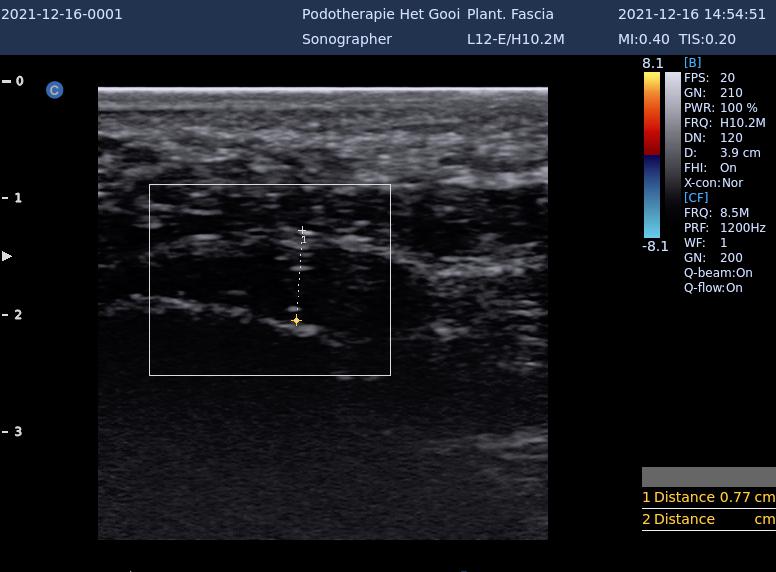

plantaire fascie echo